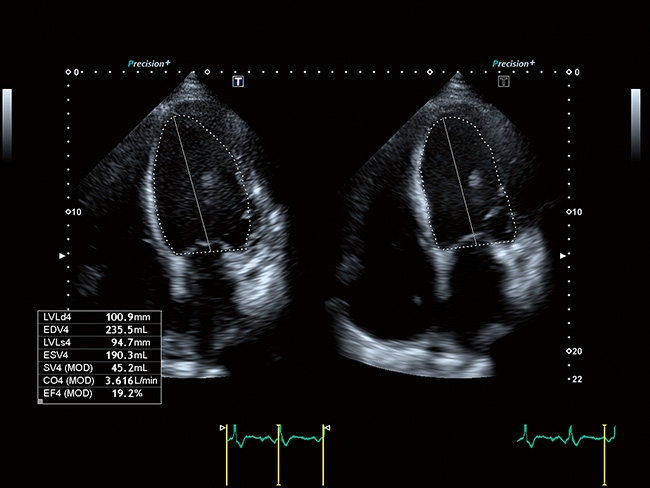

Aplio a550 может работать с линейным матричным датчиком и поддерживает новейшие монокристаллические датчики. Также Aplio a550 поддерживает большое количество дополнительных опций, таких как - SMI, Компрессионная эластография, Эластография сдвижной волны, Smart Fusion, исследования с использованием контраста (CEUS), 3D реконструкции в реальном времени (4D), функции автоматической оценки подвижности миокарда и фракции выброса.